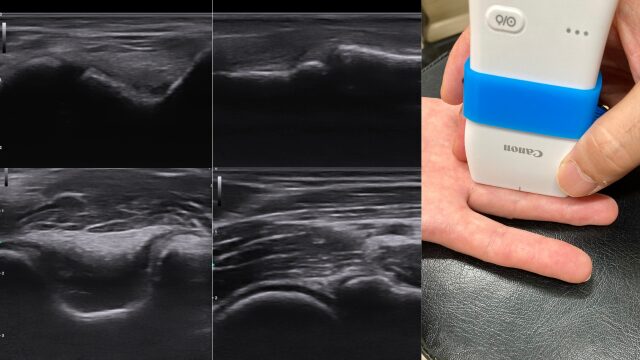

症状はもちろんのこと姿勢や動作も確認します。エコーで炎症や損傷状態、骨折の有無を観察します。体の柔軟性や筋力の偏り、身体のバランスなどが原因となって、障害が発生することがあります。体トータルでの確認が大切です。状態により、専門医への紹介も行います。